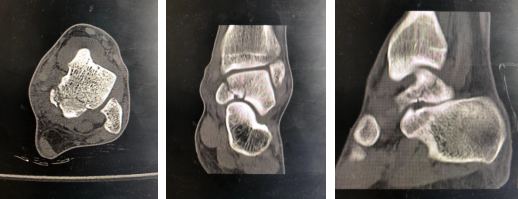

3月28日,家住徐州县区的张宇(化名)干活时不慎从1米高处摔下,左踝部受力,即感伤处肿胀疼痛,活动受限,不能站立和行走,急来betway在线登陆就诊。门诊摄X片、CT考虑距骨骨折,以“左距骨骨折”收入院。

CT